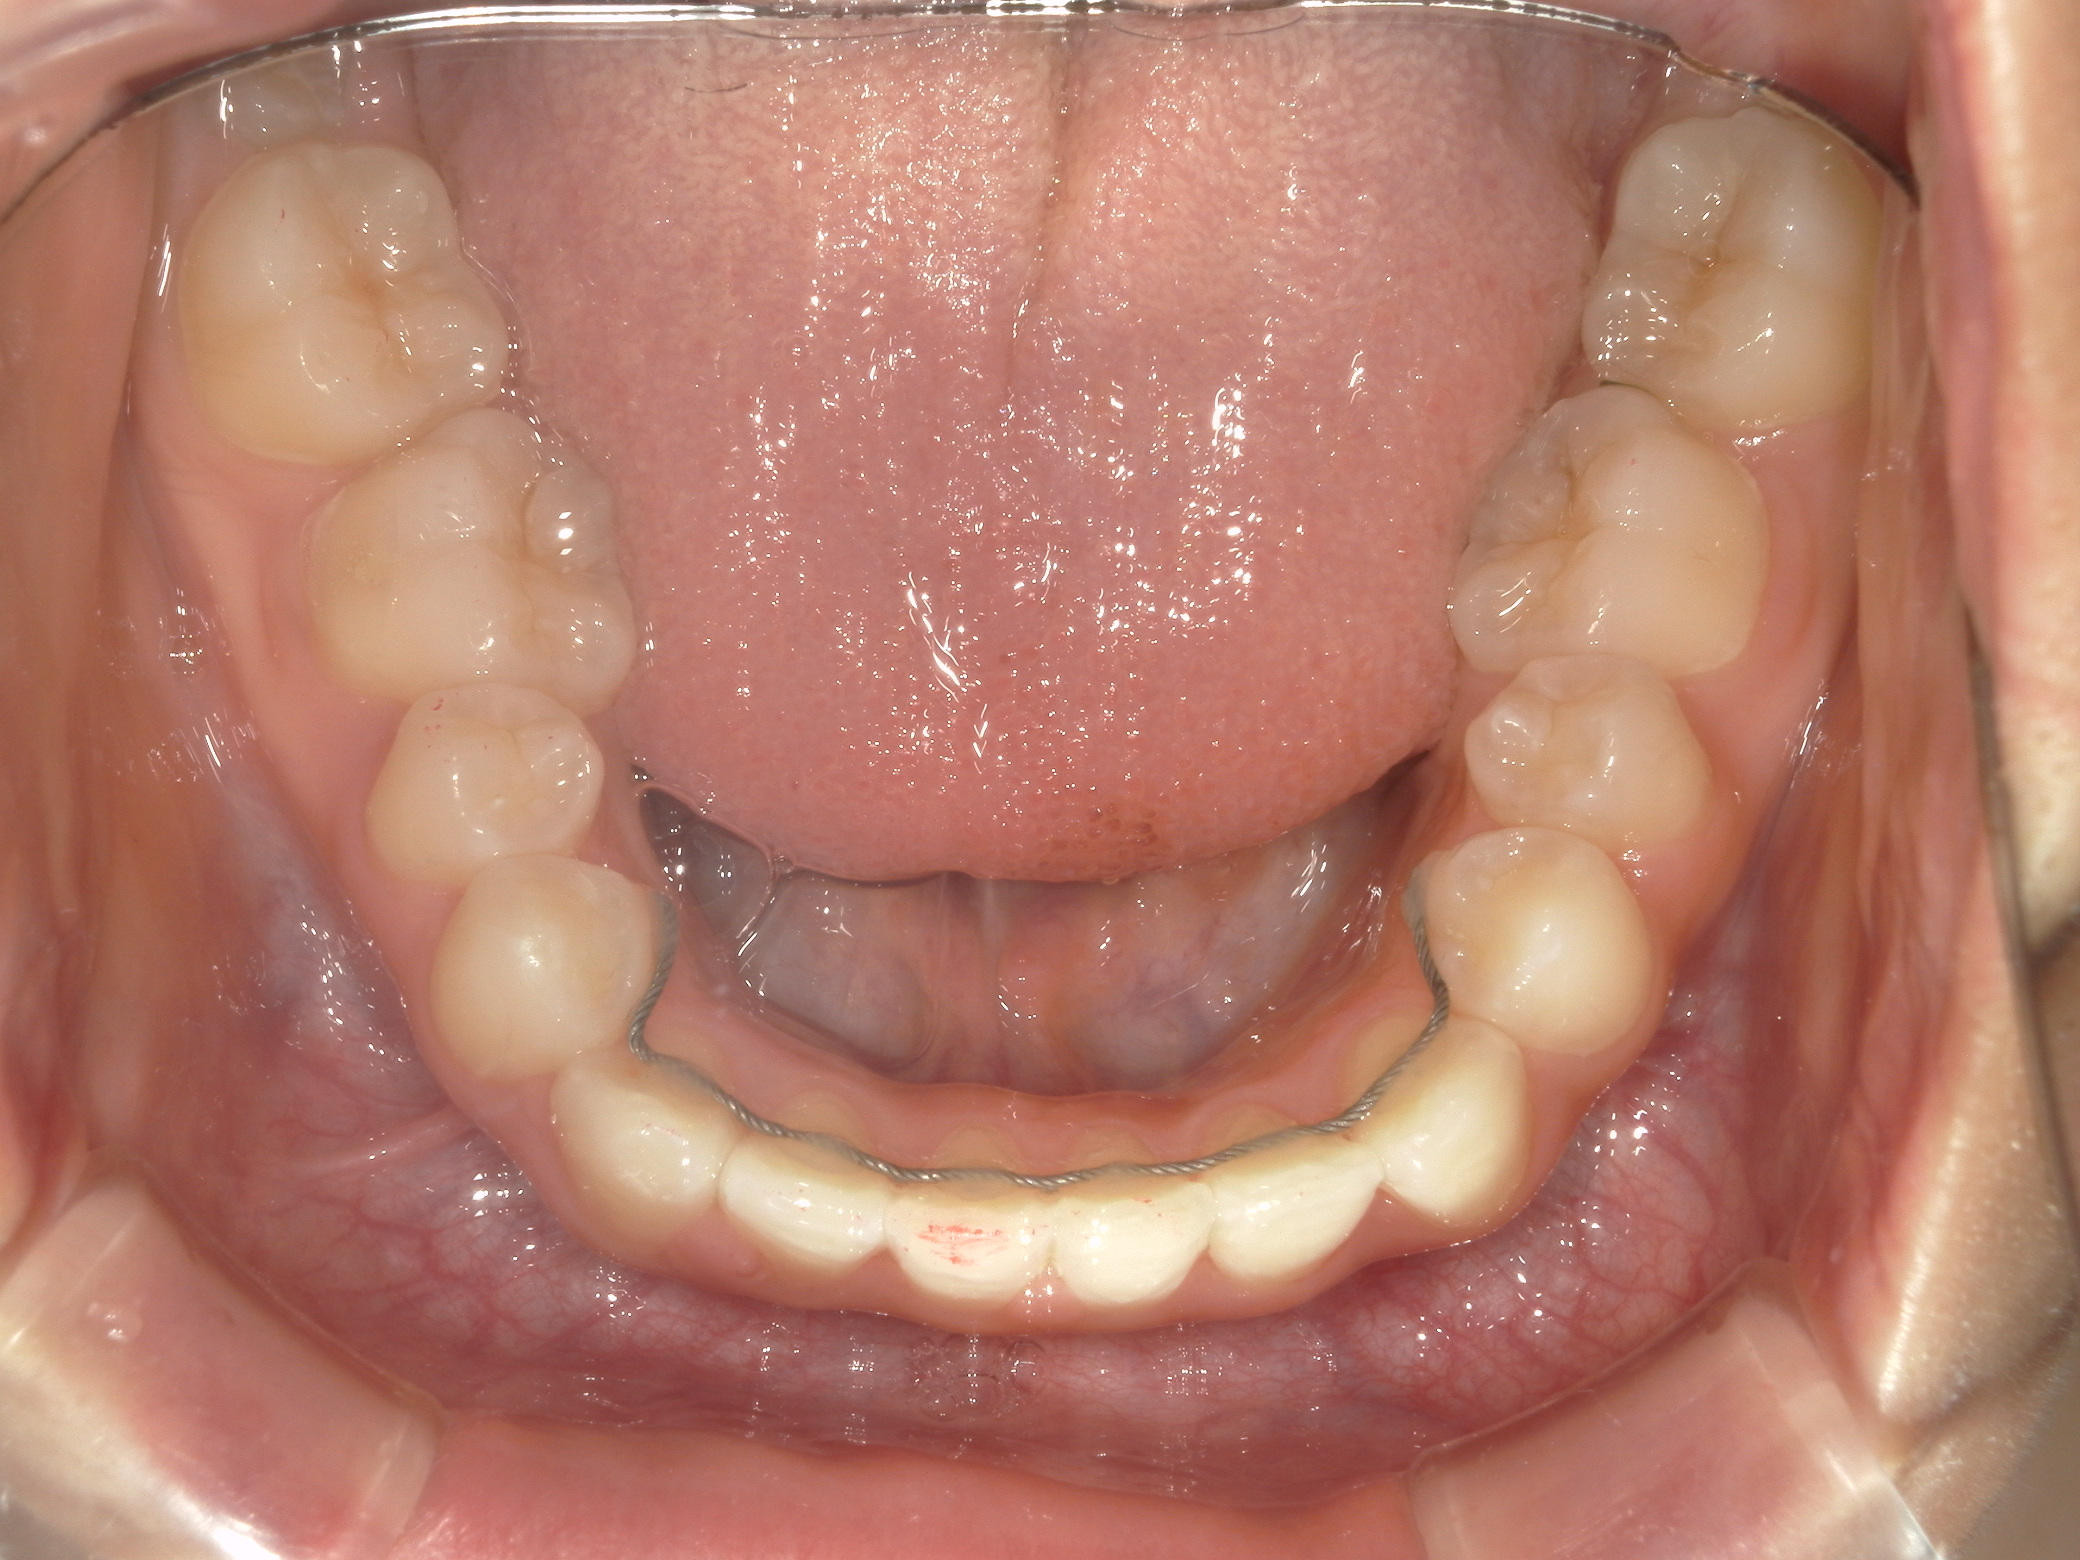

プチワイヤー矯正 症例(54)

主訴: 歯並びが気になる。

ミニインプラント(2本)、スライスカットを併用。

カテゴリー : ガタガタ(叢生)